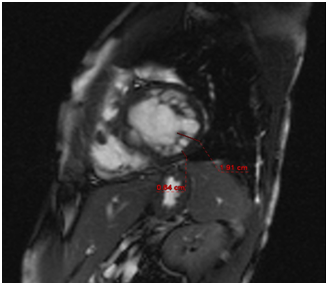

Pulmonary arterysystolic pressure was 46 mmHg, with moderate tricuspid regurgitation. No pericardial effusion was seen, and the aorta was normal with atrial septal integrity. Heart MRI revealed an altered left ventricular morphological pattern characterized by the presence of multiple trabeculae forming a reticular pattern, especially affecting the distal half of the ventricle. The interventricular septum bulged from left to right, and there was mild hypokinesia of the middle third of the interventricular septum, mainly towards its anterior half. No areas of abnormal uptake were found in the ventricular walls. There was no pericardial effusion and no infiltration of the myocardium or areas of scarring. The findings were compatible with non-compacted myocardium (Figure 1 & 2). An electrophysiological study ruled out the presence of an accessory hidden pathway. Due to the presence of an atypical slow atrial flutter fast degenerating into atrial fibrillation, no ablation was performed.

Figure 2 Long axis, bSSFP technique. The non compact component of the LV is observed. Increased size of the Left atrium is an associate finding.